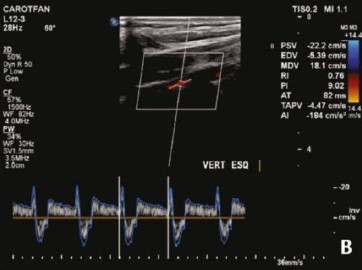

Paciente do sexo feminino, 74 anos, é encaminhada pelo cardiologista devido a vertigem, náuseas e “apagões”. AP: hipertensão arterial e labirintite.

Foi realizado ecodoppler de artérias carótidas e vertebrais, como mostra a imagem a seguir.

Assinale a alternativa que corresponde ao diagnóstico correto para a paciente nesse caso.